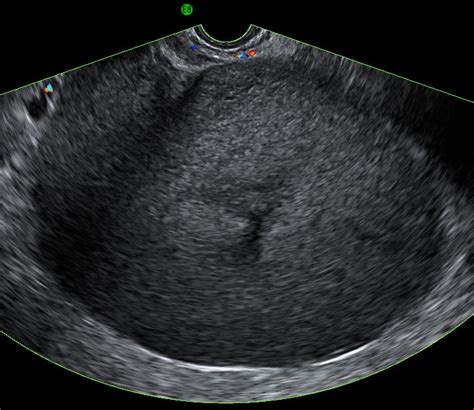

An ultrasound, or sonogram, uses high-frequency sound waves to create images of the internal structures of the body. When specifically looking for markers associated with ovarian health, doctors utilize this technology to examine the size, shape, and structure of the ovaries. Because ovarian cancer is often asymptomatic in its early stages, imaging tools play a critical role in detecting abnormalities such as cysts, solid masses, or enlarged ovaries that may warrant further investigation.

It is important to understand that an ultrasound alone cannot definitively diagnose ovarian cancer. Instead, it serves as a screening and diagnostic tool that helps specialists categorize ovarian masses as either benign (non-cancerous) or suspicious. By analyzing the characteristics of a mass, such as its internal composition, blood flow, and the presence of irregular borders, radiologists can determine the likelihood of malignancy.

• Transvaginal Ultrasound (TVUS): This is generally considered the gold standard for examining the ovaries. A slim, wand-like transducer is inserted into the vagina, placing it in closer proximity to the ovaries. This method offers much higher resolution, allowing doctors to identify subtle changes in ovarian tissue.